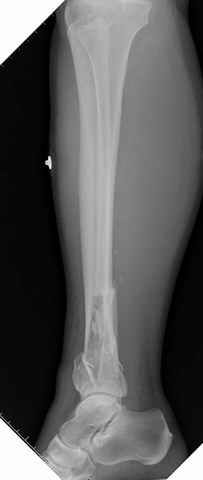

На снимках варианты фиксации малоберцовой:

№ 1 двух лодыжек

DK> На снимках варианты фиксации малоберцовой:

DK> № 1 двух лодыжек

А предоперационный снимок?